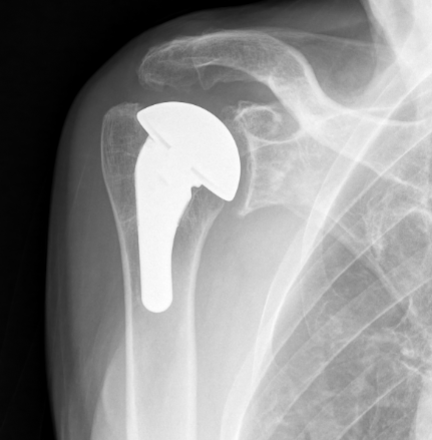

Anatomic